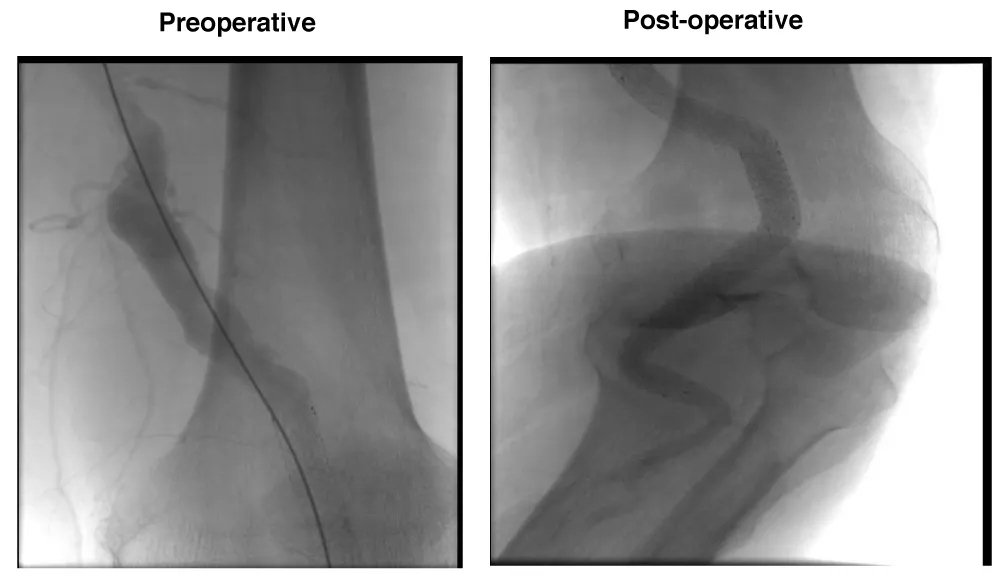

Male patient, 51 years, with arterial hypertension and a history of trauma due to gunshot. The patient evolved with a high-output arteriovenous fistula in the popliteal region causing significant symptoms and 30 mm a popliteal aneurysm. Due to this important symptom, the patient was scheduled to undergo an endovascular procedure with the popliteal implant of endoprosthesis Wrapsody® 12x80 mm at the distal neck, followed by the implant of Wrapsody 14x80 mm and two Wrapsody 16x80 mm at the proximal neck, followed by catheter balloon dilatation. (Figure 2). The patient was discharged from the hospital first day post-operative with Rivaroxaban 20 mg/day and a 6-month follow-up showed endoprosthesis patency and no endoleaks with complete resolution of the previous symptoms.

Figure 2: Endovascular treatment of a 51-year-old male with traumatic arteriovenous fistula and popliteal aneurysm (30 mm): Preoperative angiogram displays fistula formation and aneurysmal dilation. Postoperative image shows complete aneurysm exclusion using four Wrapsody® stents (12×80 mm, 14×80 mm, and two 16×80 mm), with restored vessel continuity and resolution of fistulous flow.